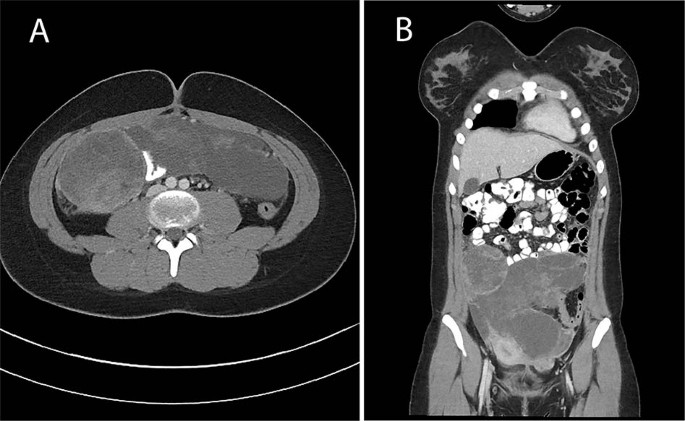

Case 4: a 14 years old previously healthy female presented with abdominal pain and urinary incontinence. CT scan showed a large mass arising from the right fallopian tube with abdominal and pelvic implants (Fig. 3). The pathologic features included embryonal rhabdomyosarcoma with heterologous cartilage and anaplasia. Further testing of the tumor tissue confirmed biallelic pathogenic mutations in DICER1. She received chemotherapy with two cycles of VAC followed by therapy per Children’s Oncology Group protocol ARST08P1 with irinotecan/temozolomide and vincristine, doxorubicin, and cyclophosphamide alternating with ifosfamide and etoposide followed by abdominal radiation. She has no evidence of disease 10 months following diagnosis.

Axial (a) and coronal (b) computed tomography images demonstrate a heterogeneous low attenuation lobulated intraperitoneal mass with nonenhancing regions suggesting intratumoral necrosis extending from the level of the umbilicus to the lower pelvis, similar in appearance to a type III PPB.